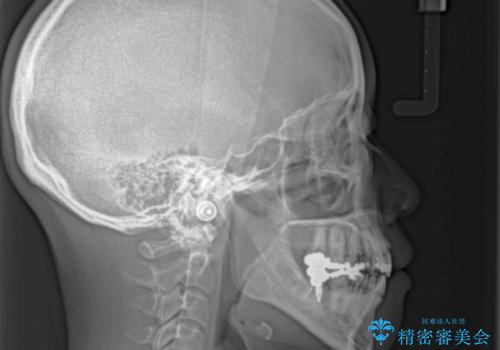

出っ歯と奥歯の欠損 ワイヤー矯正とインプラント治療

- 口元の突出感と奥歯の欠損を気にして来院された患者様です。

口元の突出感改善には、上下左右の第一小臼歯4本を抜歯し、奥歯の欠損部には矯正治療の途中でインプランを埋入していくこととしました。

矯正治療の後半にインプラント埋入を行うことで、トータルの治療期間を短縮することができました。